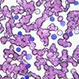

How Does Leukemia Kill?Leukemia is a cancer of the white blood cells of the bone marrow. Patients with leukemia have an over-production of a particular blood cell type in the body, the white blood cells (cells that fight infection, and provide immunity).

Is CLL a Disability?Leukemia is the cancer of the white blood cells of the bone marrow (spongy part of long bones). Patients with leukemia have an overproduction of a type of blood white cell in the body. In chronic lymphocytic leukemia (CLL), the bone marrow produces too many immature lymphocytes (a type of white cells).